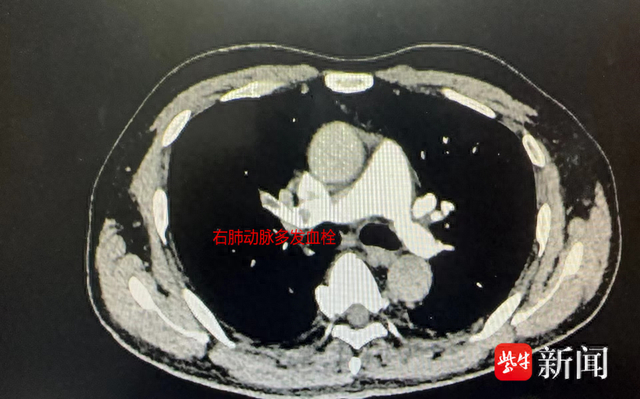

50岁的周先生的右腿水肿已一个月有余,加上开始有胸闷症状,于是来到江苏省中西医结合医院就诊。心血管科副主任医师吴溧兴在接诊中了解到,周先生是一名长途车司机,一般四个小时才停车休息一下,开车时也很少饮水,还有长期的饮酒和吸烟史。通过双下肢动静脉彩超和肺动脉CTA检查发现,他的右侧下肢股总静脉及其以下分支血栓形成,右肺动脉主干、右肺动脉及左下肺多分支肺动脉栓塞。随后,周先生被安排住院治疗,经过积极的抗凝治疗,他下肢水肿及血氧等各项指标逐渐恢复正常。出院时,吴主任还特别叮嘱周先生继续口服抗凝药物,暂时不要长途驾驶,要戒烟戒酒,足量饮水,适当活动。一月后,周先生再次来到医院复查,下肢静脉彩超显示血栓消失。